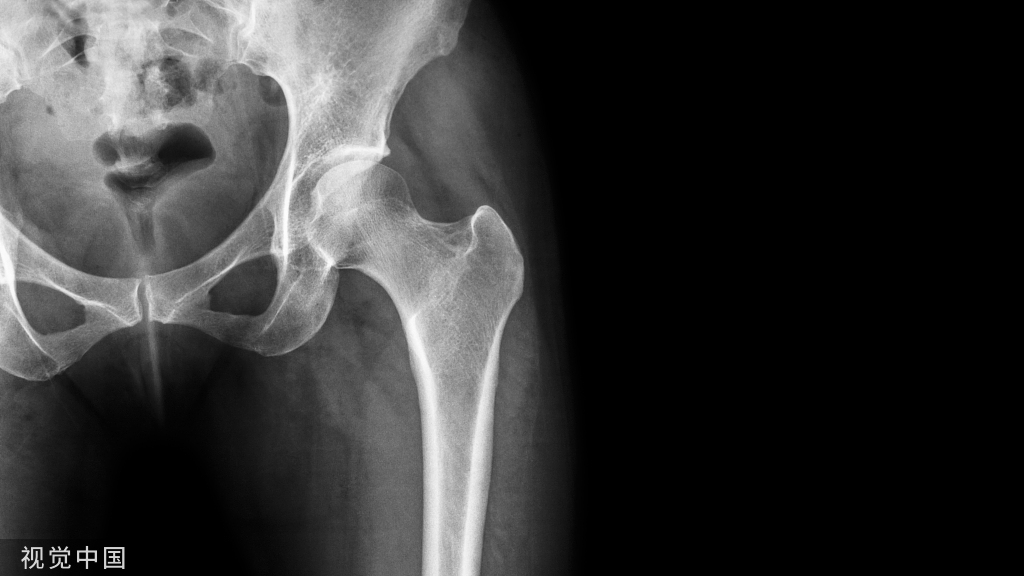

LISS微创固定系统应用技巧,原来如此简单!